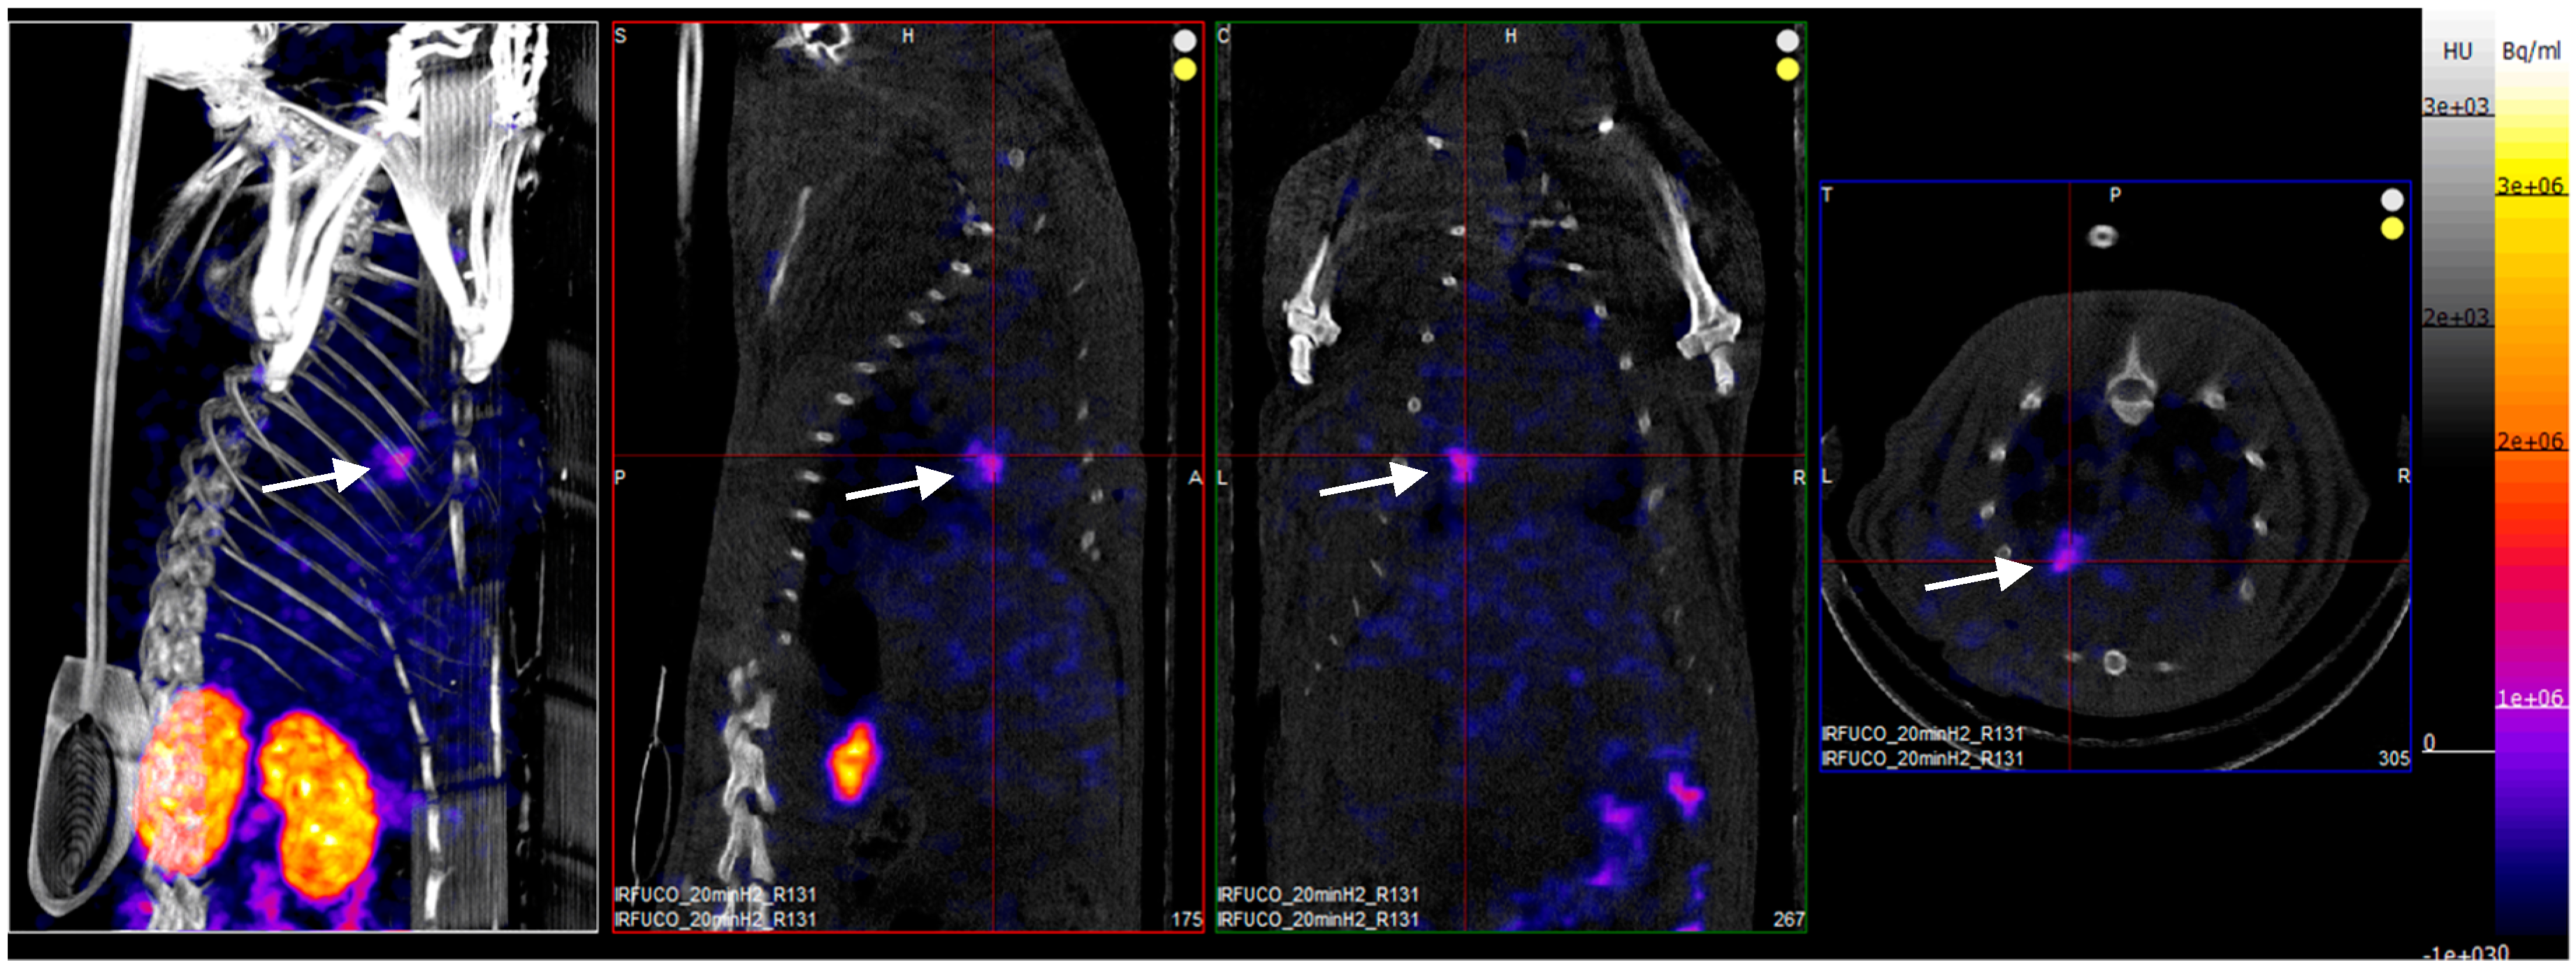

Four hours after reperfusion, a clear focal uptake of GMP grade LMW fucoidan labeled with 99mTc (Investigational Medicinal Product) had been detected in all animals confirming the presence of exposed P-selectin [18], either by endothelium cells or by activated platelets in the area of myocardial ischemia (Figure 3).

Figure 3. SPECT/CT scans of an ischemia-reperfusion rat model acquired 2 h after intravenous injection of GMP grade LMW fucoidan labeled with 99mTc (Investigational Medicinal Product) (white arrows). Representative whole body SPECT/CT imaging: from left to right: 3D view, sagittal, coronal, and axial planes.

70 MBq radiolabeled fucoidan was injected (penis vein) after 2 h of reperfusion. The SPECT/CT images were acquired 2 h after injection, using a nanoSPECT/CT apparatus (Mediso 30 medical imaging systems, Hungary) with a four-headed multiplexing multipinhole camera. Each head was equipped with a tungsten collimator (rat whole body—high sensitivity).